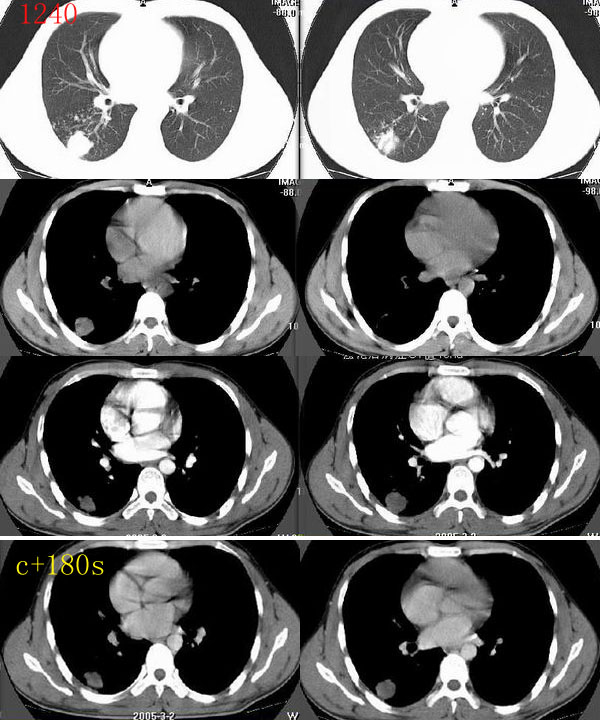

ct1240:song7715

病人24岁,身体偏瘦,半月前曾有高烧,现无阳性体征,血项不高。透视时无意发现。

右肺结节病理结果:结核球http://www.radida.com/radinet/read.php?tid=3611